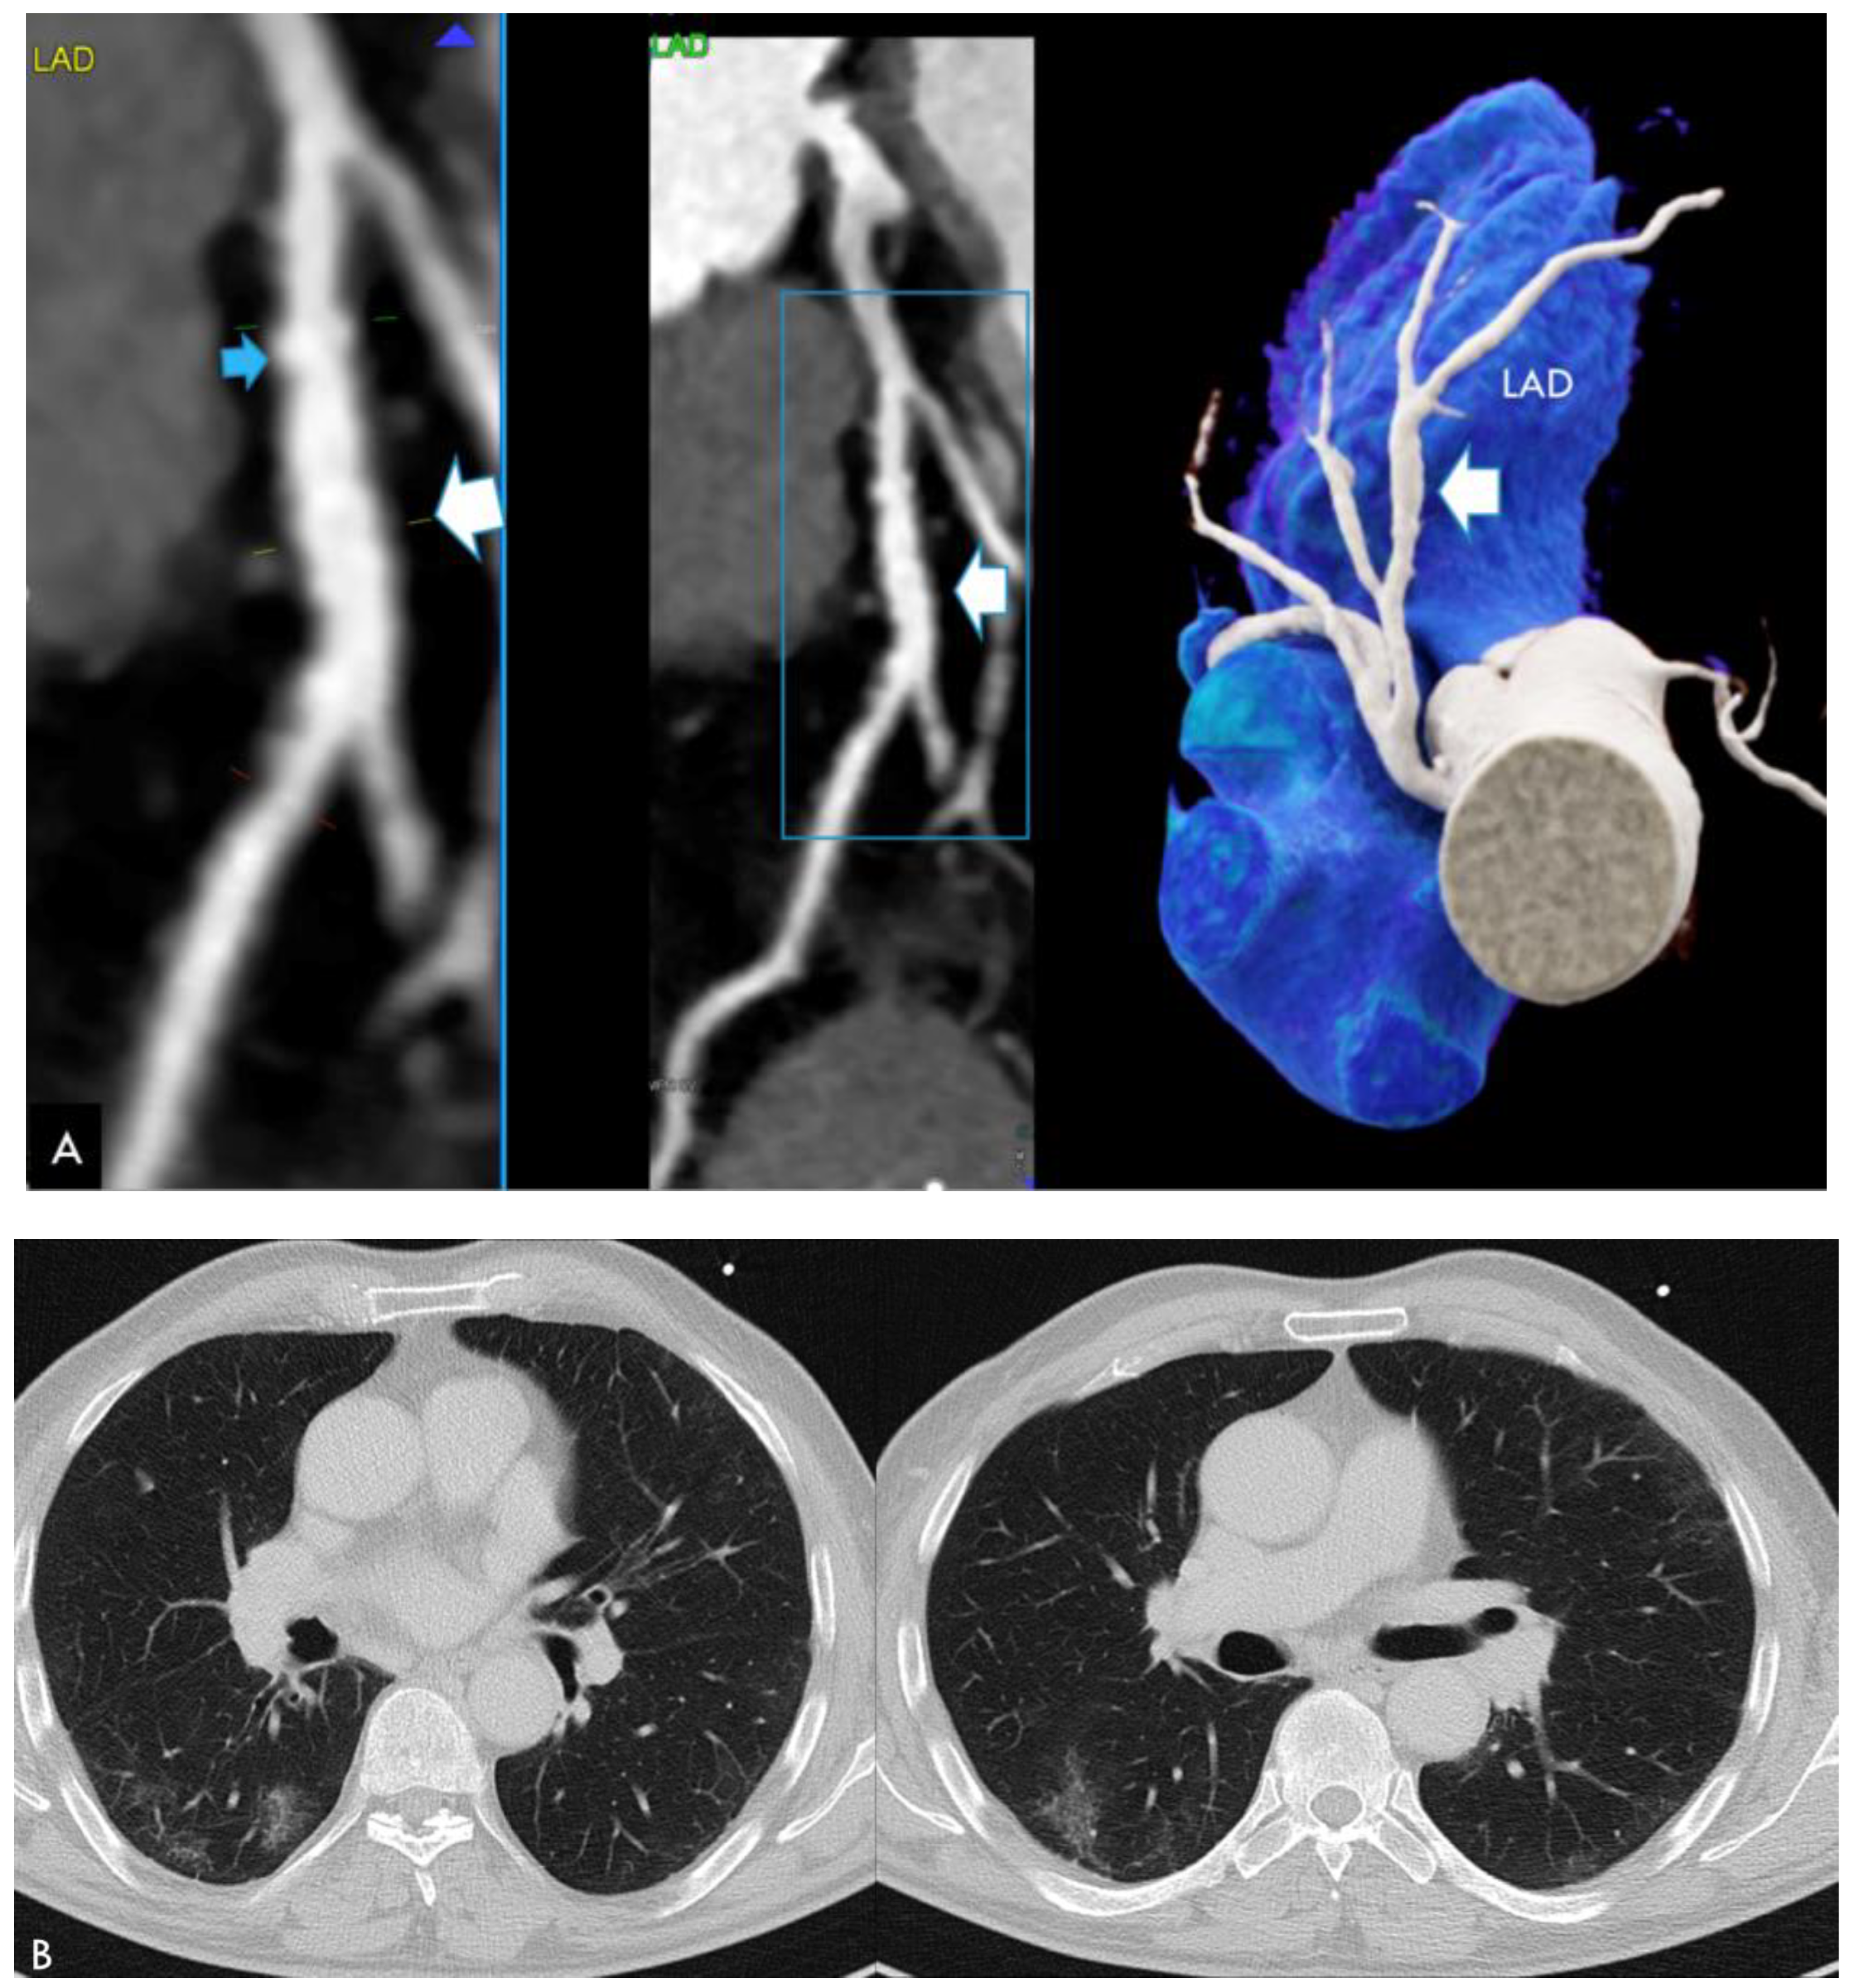

| CTA findings | ||

| Acute, unstable N = 4 | Stable N = 8 | |

| Coronary artery disease by CTA | 1 (25%) | 4 (50%) |

| Nonobstructive (<50% stenosis) | 0 (0%) | 2 (25%) |

| Obstructive (>50% stenosis) | 1 (25%) | 2 (25%) |

| Diffuse vessel wall irregularities | 2 (50%) | 3 (37.5%) |

| Focal ectasia | 0 (0%) | (12.5%) |